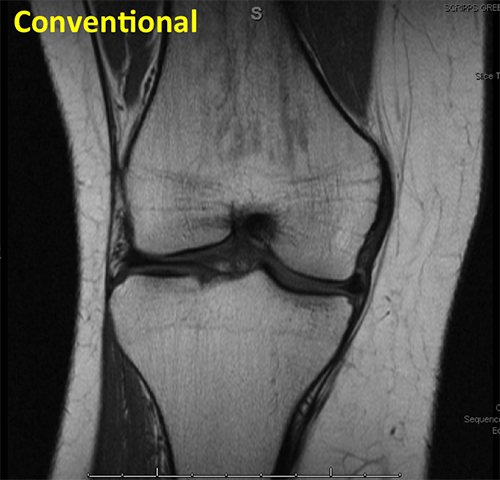

Knee Conventional

This conventional MRI of a knee shows articular cartilage and menisci with medium to low signal intensity.